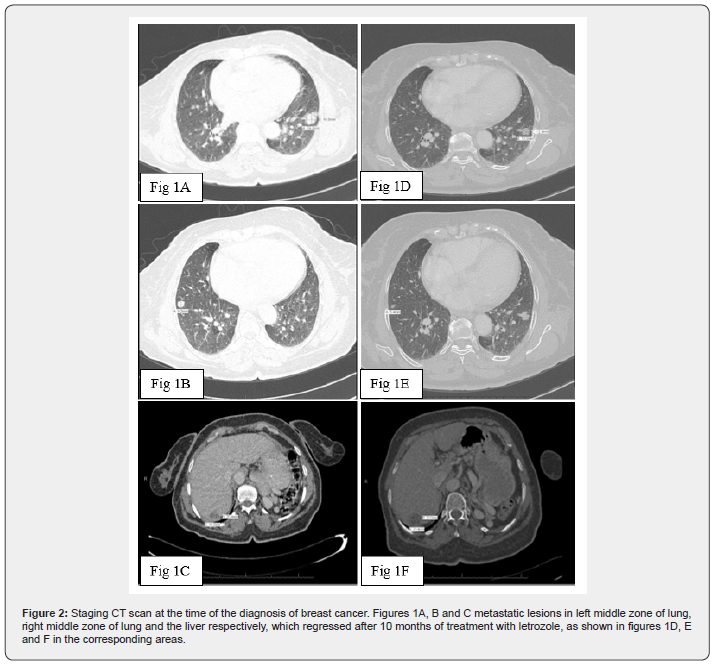

At this stage the CA-125 was seen to rise again serially, and mammogram showed a 2.2 cm speculated lesion in the left breast. A fine needle aspiration was highly suggestive of breast cancer, and a core biopsy revealed an infiltrating ductal carcinoma, grade II, estrogen and progesterone receptor positive, but negative for HER-2/neu protein (ER positive; PR positive; HER-2/neu negative). The proliferation fraction measured by Ki-67 was 40%. The morphologic and immunohistochemical patterns were consistent with a diagnosis of a primary in the breast (Table 1). Staging CT scan revealed a metastatic lesion in liver and bilateral pulmonary metastases. An attempt at guided biopsy from the pulmonary lesion was unsuccessful and led to pneumothorax. The patient refused further attempt at biopsy and agreed to be treated with Letrozole, considering that the pattern of metastases was more likely secondary to breast cancer rather than the ovarian cancer. Ten months later, the CT scan showed a marked regression in the size of pulmonary lesions, but a stable liver lesion (Figure 2).